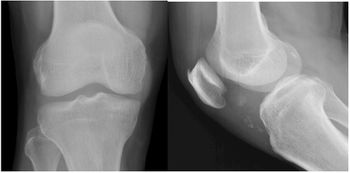

Case History: 58-year-old male with intermittent mild pain in left knee. No previous remarkable trauma; no correlation between pain and physical activity.